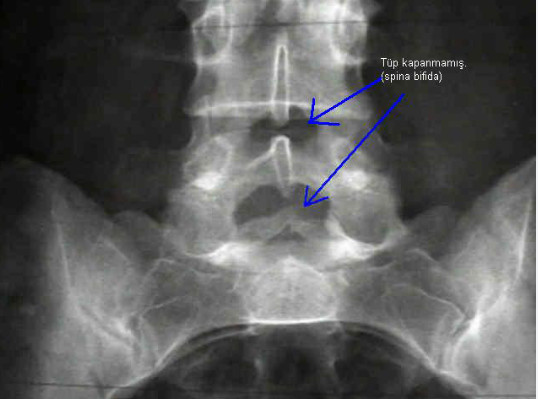

- X quang: X quang là xét nghiệm đầu tay giúp xác định tổn thương gai đôi cột sống. Ưu điểm của kỹ thuật này là đơn giản, nhanh chóng, tiết kiệm, tuy nhiên nhược điểm lại khiến trẻ bị phơi nhiễm tia X.

- Gai đôi cột sống bẩm sinh thể ẩn: đây là loại gai đôi cột sống nhẹ nhất với một khoảng trống nhỏ ở cột sống nhưng không có lỗ hở hay túi phình phía sau, bệnh nhân không bị rối loạn chức năng tủy sống. Dạng này được phát hiện tình cờ trên X quang hoặc được phát hiện khi trẻ đến tuổi trưởng thành.